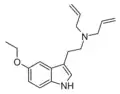

| Chemical structure | Short Name | Origin | Ring Substitution | RN1 | RN2 | Full Name | CAS Number |

|---|---|---|---|---|---|---|---|

| DALT | artificial | H | H2C=CH-CH2 | H2C=CH-CH2 | N,N-diallyltryptamine | 60676-77-9 |

| 5-MeO-DALT | artificial | 5-OCH3 | H2C=CH-CH2 | H2C=CH-CH2 | 5-methoxy-N,N-diallyltryptamine | 928822-98-4 |

| 5-Ethoxy-DALT | artificial | 5-OCH2CH3 | H2C=CH-CH2 | H2C=CH-CH2 | 5-ethoxy-N,N-diallyltryptamine | |